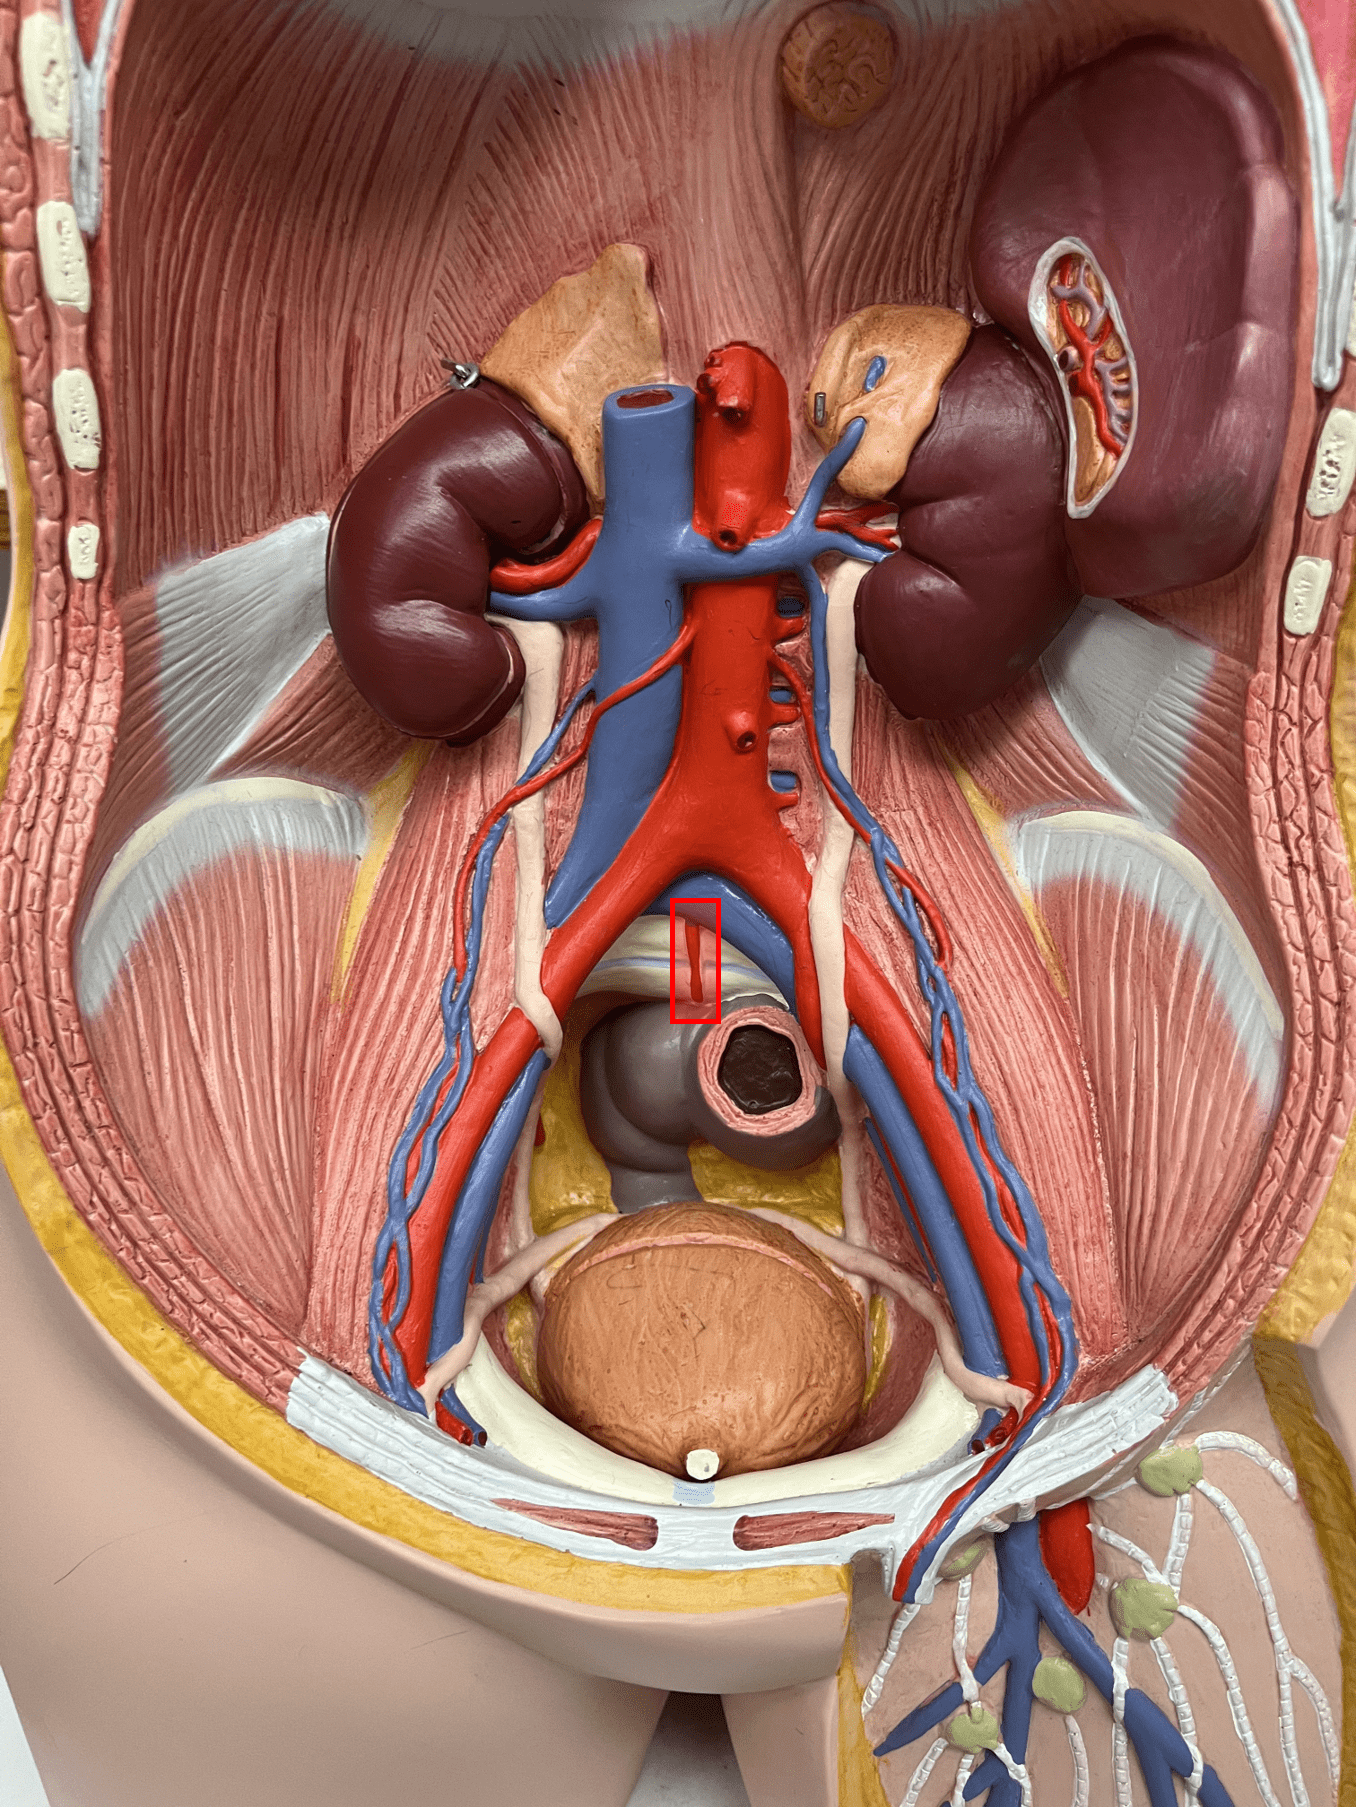

• Found between the tunica externa and tunica media.

median sacral artery

• An artery of the abdomen.

• Originates from the abdominal aorta.

• Supplies the sacrum and coccyx.

• Originates from the abdominal aorta.

• Supplies the sacrum and coccyx.